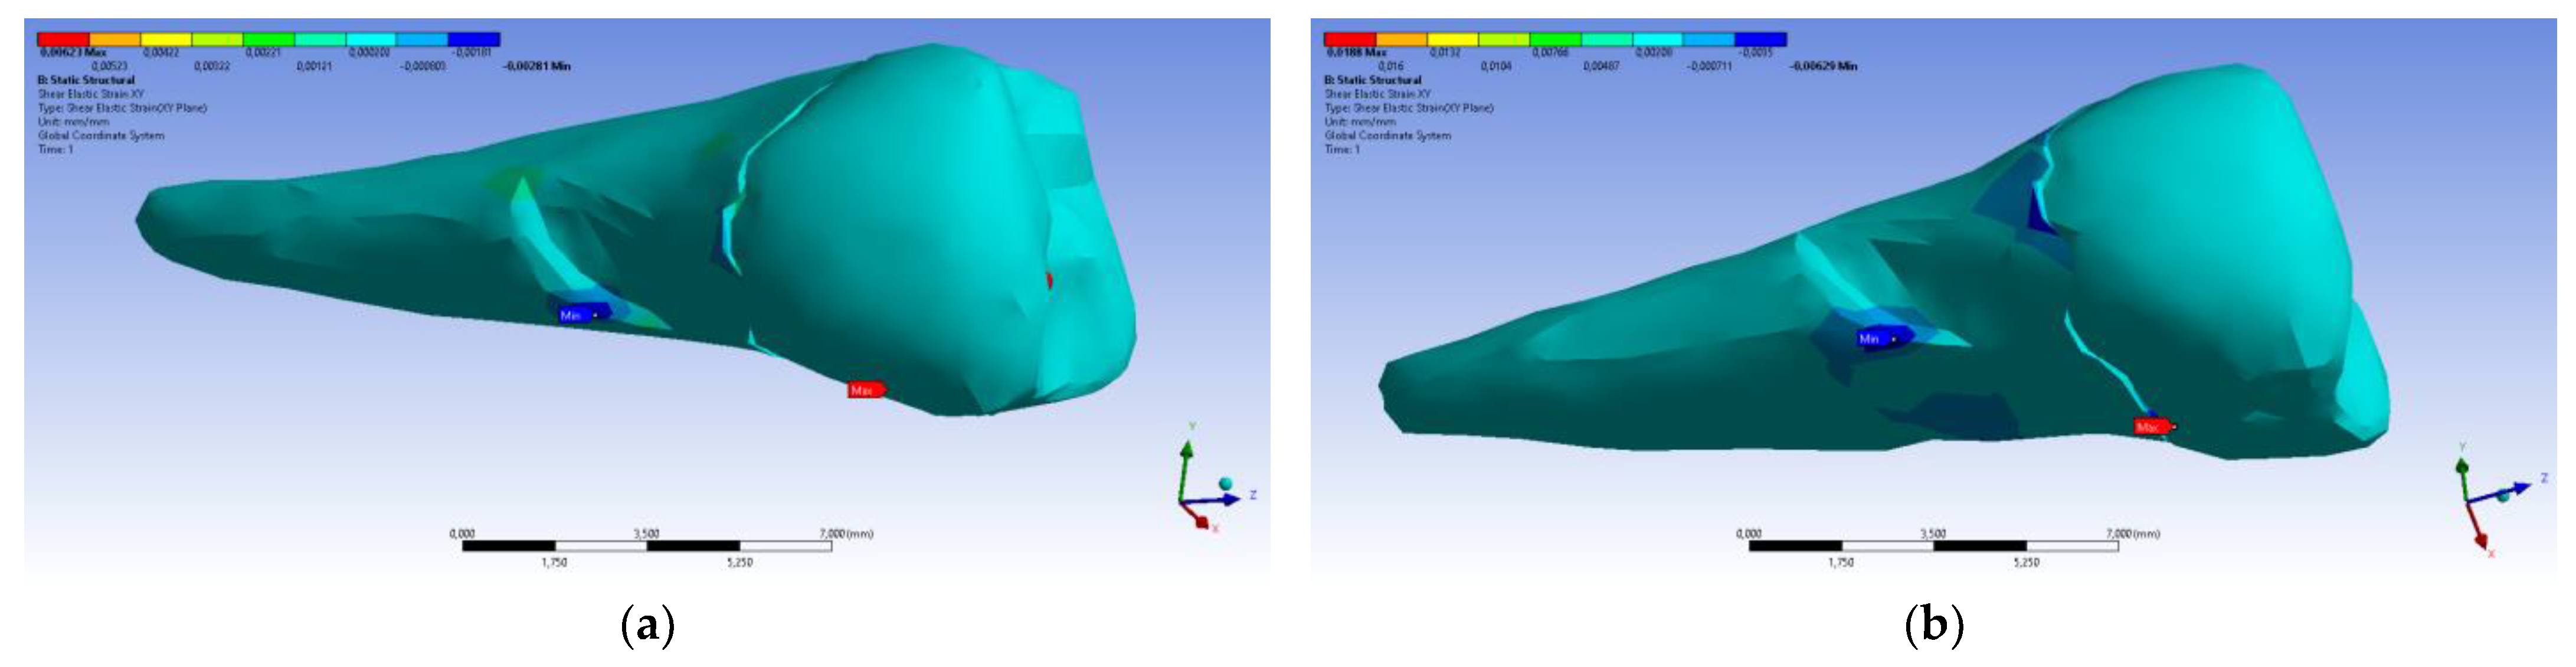

3. Finite Element Analysis (FEA) of Mandibular Right Premolars

| Maximum Tangential Stress | Main Elastic Relative Deformation | Main Maximum Elastic Relative Deformation | Main Minimum Elastic Relative Deformation | Maximum Tangential Elastic Relative Deformation | Relative elastic Normal X Deformation | Relative Elastic Normal Y Deformation | Relative Elastic Normal Z Deformation | Relative Elastic Tangential XY Deformation | Relative Elastic Tangential YZ Deformation | Relative Elastic Tangential XZ Deformation | |||

| Minimum | 5.4 × 10−7 MPa | 6.36 × 10−11 mm/mm | −1.33 × 10−5 mm/mm | −1.05 × 10−2 mm/mm | 7.6 × 10−11 mm/mm | −2.26 × 10−3 mm/mm | −1.43 × 10−3 mm/mm | −3.45 × 10−3 mm/mm | −2.81 × 10−3 mm/mm | −4.09 × 10−3 mm/mm | −7.93 × 10−3 mm/mm | ||

| Maximum | 143 MPa | 1.33 × 10−2 mm/mm | 9.66 × 10−3 mm/mm | 1.09 × 10−5 mm/mm | 2.01 × 10−2 mm/mm | 1.37 × 10−3 mm/mm | 1.89 × 10−3 mm/mm | 3.14 × 10−3 mm/mm | 6.23 × 10−3 mm/mm | 1.65 × 10−2 mm/mm | 3.13 × 10−3 mm/mm | ||

| Minim. in | Cementum | Cementum | Enamel | Cementum | Cementum | Cementum | Cementum | Cementum | Cementum | Cementum | Cementum | ||

| Maxim. in | Cementum | Cementum | Cementum | Cementum | Cementum | Cementum | Cementum | Enamel | Cementum | Cementum | Cementum |